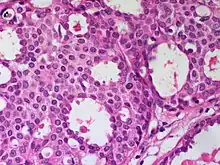

| Cribriform carcinoma of the breast showing a cribriform area | |

Invasive cribriform carcinoma of the breast (ICCB), also termed invasive cribriform carcinoma, is a rare type of breast cancer that accounts for 0.3% to 0.6% of all carcinomas (i.e. cancers that develop from epithelial cells) in the breast.[1] It originates in a lactiferous duct as opposed to the lobules that form the alveoli in the breasts' mammary glands (lobules make the milk which the ducts channel to the breast's nipple). ICCB was first described by Dixon and colleagues in 1983 as a tumor that on microscopic histopathological inspection had a cribriform pattern,[2] i.e. a tissue pattern consisting of numerous "Swiss cheese"-like open spaces and/or sieve-like small holes (see adjacent Figure).[3] The latest edition (2019) of the World Health Organization (2019) termed these lesions invasive cribriform carcinomas indicating that by definition they must have a component that invades out of their ducts of origin into adjacent tissues. In situ ductal cancers (i.e. cancers localized entirely within their tissues of origin) that have a cribriform histopathology are regarded as belonging to the group of ductal carcinoma in situ tumors.[4]

The microscopic histopathology of ICCB tumors stained with hematoxylin and eosin shows cribriform areas covering more than 50% of the tumor with the remaining tumor areas showing tubular and/or other histopathological patterns. The cribriform areas consist of small-sized cells with amphophilic (i.e. taking up both the hematoxylin and eosin stains) cytoplasm, indistinct cell boundaries, and small-to-medium sized nuclei that are surrounded by a sharp nuclear membrane and contain finely stippled chromatin (i.e. DNA coated with protein).[17] Numerous open spaces and/or sieve-like small holes lie between these cells (see above photomicrograph) to give the lesions a Swiss cheese-like appearance. The spaces and holes may contain microcalcifications and/or mucins (i.e. high molecular weight, sugar-linked proteins normally produced and secreted by the mammary gland and found in milk).[3] The cells around these spaces and holes sometimes have "apical snouts", i.e. small protrusions on the side of the cells that faces the spaces and holes.[11] Tubular areas (see adjacent photomicrograph of a tubular carcinoma) consist of well-formed tubules lined with mostly normal appearing tubular cells.[17][20] The other histopathological patterns that may occur in these tumor types include the pattern associated with invasive carcinoma of no special type[4] or in uncommon cases the pattern associated with mucinous carcinoma of the breast.[17] The invasive component of these tumors almost always has the cribriform histopathology pattern.[14] All of the tumor cells in ICCB are typically slow-growing as evidenced by their low mitotic index (i.e. the ratio of the number of dividing cells to the total number of tumor cells) or low levels of cellular Ki-67 protein (an index of cell proliferation).[14]